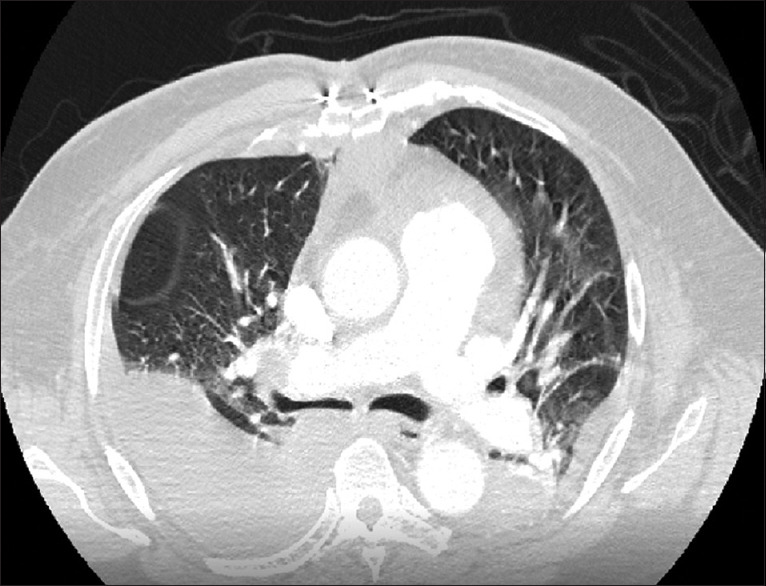

Abstract: This study describes the perioperative management of a 68-year-old Jehovah's Witness patient with chronic pulmonary thromboembolism, multiple comorbidities, and undergoing pulmonary thromboendarterectomy. The patient had a satisfactory perioperative evolution, demonstrating the feasibility of this complex procedure in this population with a comprehensive and timely approach, complemented by an evaluation from a multidisciplinary team.

Abstract Image